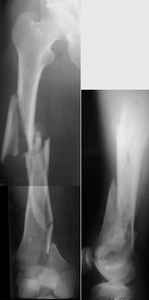

KEMMD> A. Difficult reductions, even in retrograde nailing (my preference, easier

KEMMD> control of "small" distal fragment) and it is much, much harder to do it

KEMMD> anterograde

I presented a series of ~25 such cases at EuroTrauma'2004. Many cases were discussed here. I attach am example. Look also recent cases at http://www.hwbf.org/hwb/conf/alex58/scfx.htm,

KEMMD> Malpositioning is much too common (recurvatum, varus - valgus).